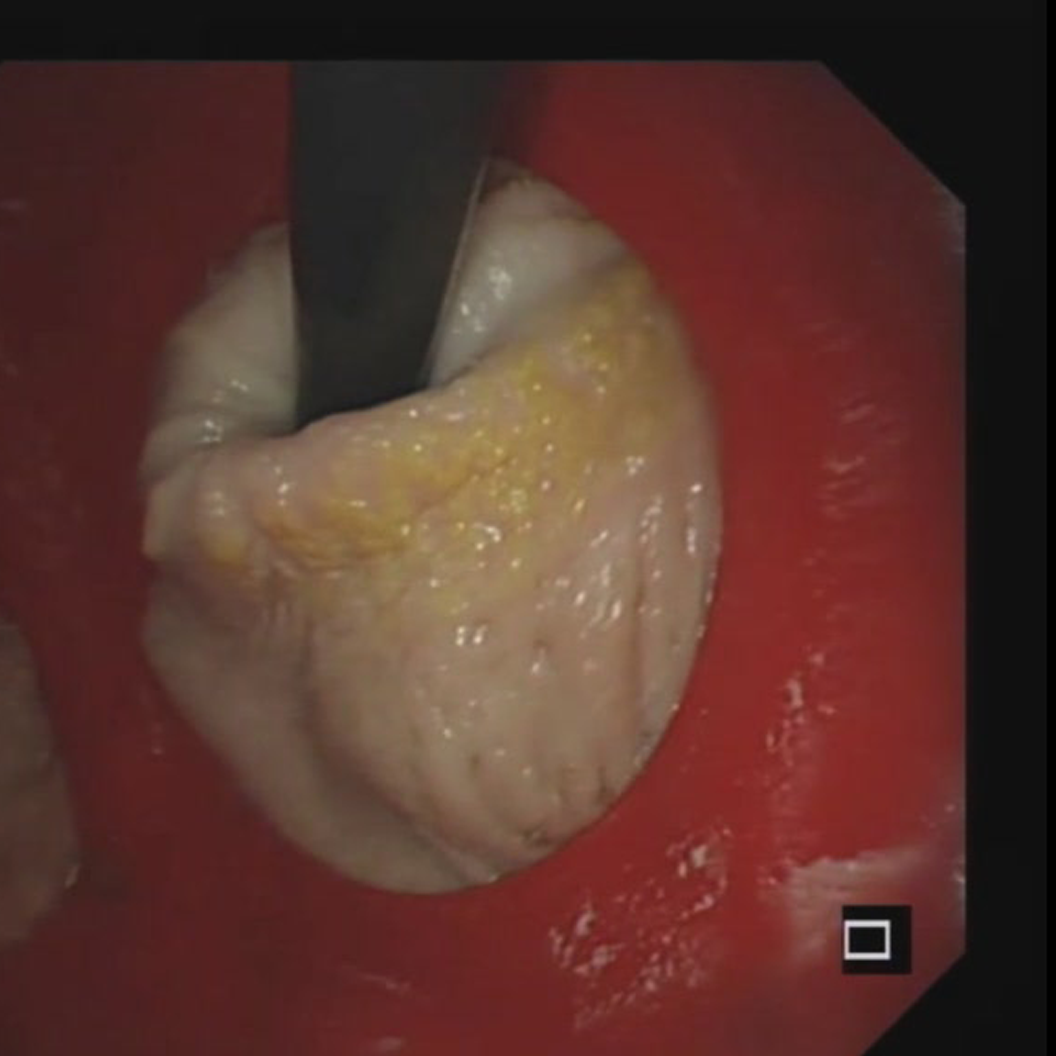

胃模型可以帮助练诊断技能。把它和模拟胃镜设备连起来,能还原真实做胃镜时的视野变化:从食管入口进胃腔的时候,得调整镜身角度,适应贲门的生理弯曲,不然镜头碰到胃壁,视野就糊了;

在胃里观察的时候,还能充气模拟胃腔扩张,把胃底、胃体、胃窦各个区域的黏膜看得清清楚楚,练怎么找那些小病变;

更重要的是,还能模拟取活检——在指定的病变位置用活检钳操作,练怎么掌握力度和角度,精准夹取黏膜组织。

这步可是临床上用胃镜确诊胃病的关键,光靠看书根本练不会。